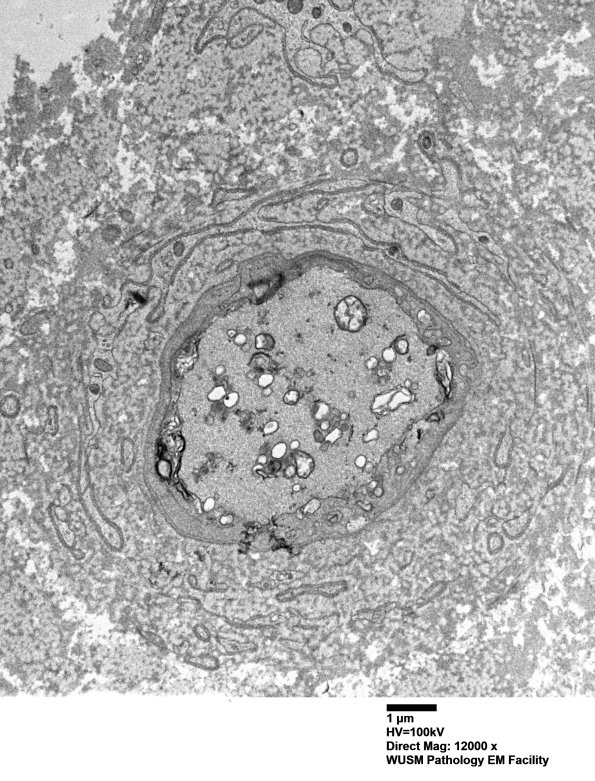

In this axon the intra-axonal process appears similar; however, what are the proliferative membranes exterior to the axon borders? (electron micrograph)